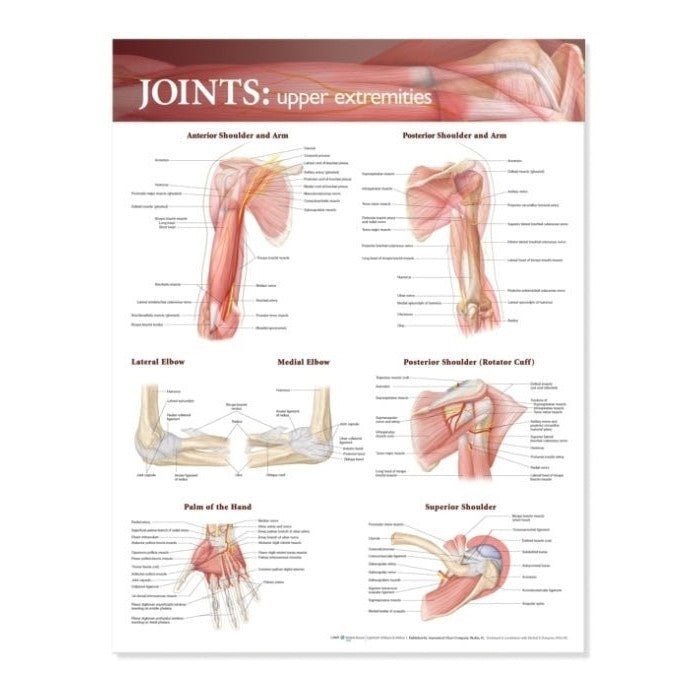

Muscle posters

Muscles provide movement to the musculoskeletal system, and their origins, insertions and lodges are clinically important for every healthcare professional. That is why we at eAnatomi have both developed and designed our own anatomy posters, which provide the ultimate overview of all the muscles of the body. On this page you can find both our own posters and posters from other manufacturers. We offer posters in several different languages such as pure Latin, Danish, English and Swedish, etc.